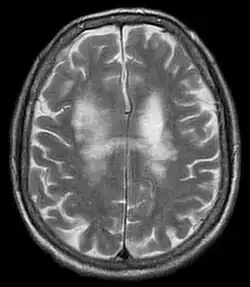

Eine relativ sichere Diagnose ist nur durch den Nachweis der JC-Virus-DNA im Liquor cerebrospinalis mittels Polymerasekettenreaktion (PCR) möglich. Der Nachweis des Virus im Urin lässt keinen Zusammenhang mit der Erkrankung zu, da etwa 20 % der Bevölkerung das Virus dauerhaft ausscheiden. Die relativ unspezifischen Demyelinisierungsherde, die mit einer Magnetresonanztomografie (MRT, Kernspintomografie) nachgewiesen werden können, können einen Beitrag zur Verdachtsdiagnose leisten. Die Herde stellen sich bei T1-Wichtung hypointens, in der T2- und Flair-Sequenz hyperintens dar und nehmen kein Kontrastmittel auf. Typisch sind flächig konfluierende und symmetrische Signalveränderungen unter Aussparung der Hirnrinde. Diese liegen oft parietal. Eine Differenzierung zu anderen Veränderungen gleichen Aussehens (zum Beispiel bei der Multipler Sklerose (MS) oder dem Posterioren reversiblen Enzephalopathiesyndrom (PRES)) ist ohne Krankengeschichte aufgrund der MRT-Befunde allein nicht möglich. Das Virus kann auch elektronenmikroskopisch in Hirngewebe nachgewiesen werden.